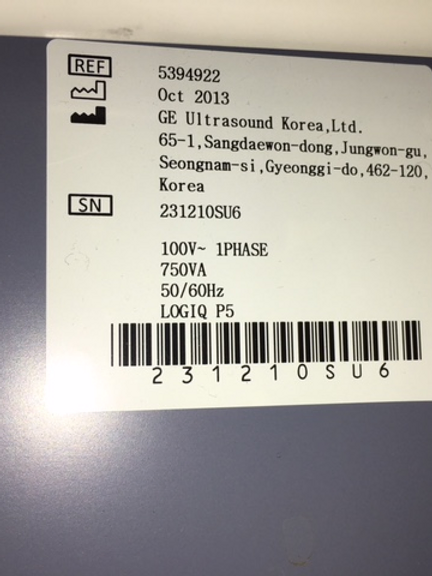

Elevate Your Diagnostic Experience with the LOGIQ P5 Ultrasound Scanner

Introduction: Experience cutting-edge imaging technology at an affordable price with the LOGIQ P5 Ultrasound Scanner. Compact, ergonomic, and packed with high-end features, this ultrasound device redefines diagnostic excellence without breaking the bank.

Unrivaled Imaging Capability: From gynaecology/obstetrics to urology, cardiology, and paediatrics, the LOGIQ P5 delivers exceptional 3D/4D imaging across a range of medical specialties. With its advanced features, it stands as the most powerful system in its price range, offering unmatched diagnostic precision and clarity.

Enhanced Functionality: Equipped with a 15-inch TFT LCD monitor and a flexible monitor arm, the LOGIQ P5 ensures optimal viewing comfort and convenience during procedures. With a spacious 50 GB hard disk for image storage and directional power Doppler imaging, it meets the demands of modern healthcare settings.